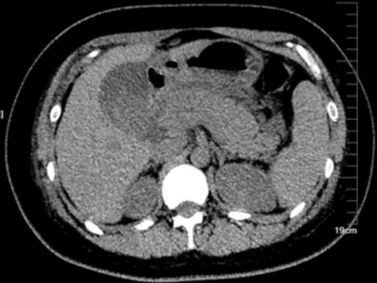

新年亲朋好友相聚在一起,围坐火锅旁,牛肉、羊肉轮着来,大鱼大虾也不缺,在开心大吃及开怀畅饮之余,一次胰腺的“自卫反击战”已打响,是否有些人吃着吃着就突然腹痛了,很有可能就得了急性胰腺炎。 急性胰腺炎是个自我消化作用导致的疾病,胰腺里面保存了很多消化液,没犯病时“乖乖的呆着”,对食物消化有着领导作用;可一旦人们暴饮暴食和酗酒,消化液就会“跑出来”开始消化胰腺自己,严重的甚至消化周围的器官,导致胰腺和周围组织坏死。急性胰腺炎分为轻型(水肿型)和重型(出血坏死型)两种,临床上轻型病人约占90%,重型占10%。其中出血坏死型胰腺炎特别凶险,常并发中毒性休克和多器官功能衰竭,死亡率极高,让患者命悬“胰腺”。 急性胰腺炎在影像上分为:间质水肿性胰腺炎、急性坏死性胰腺炎。 间质水肿性胰腺炎 胰腺肿大,边缘模糊,胰周积液 间质水肿性胰腺炎CT特征: ①胰腺体积弥漫性增大,密度正常或为均匀、不均匀轻度下降,渗出明显者除胰腺轮廓模糊外,还可有胰周积液。 ②增强扫描,胰腺均匀强化,无不强化的坏死区。 坏死性胰腺炎 坏死性胰腺炎CT特征: ①胰腺体积常有弥漫性明显增大,胰腺水肿则CT值降低,坏死区的CT值更低;而出血区的CT值明显增高,整个胰腺密度显得很不均匀;增强扫描坏死区无强化而对比更明显; ②胰周出现明显积液,常首先累及左侧肾旁前间隙; ③肾筋膜可因炎症而增厚。 胰腺炎虽然凶险,但通过影像检查可以早期发现,完全可以降低其对健康的威胁。祝大家以后的日子都能“胰”路平安。